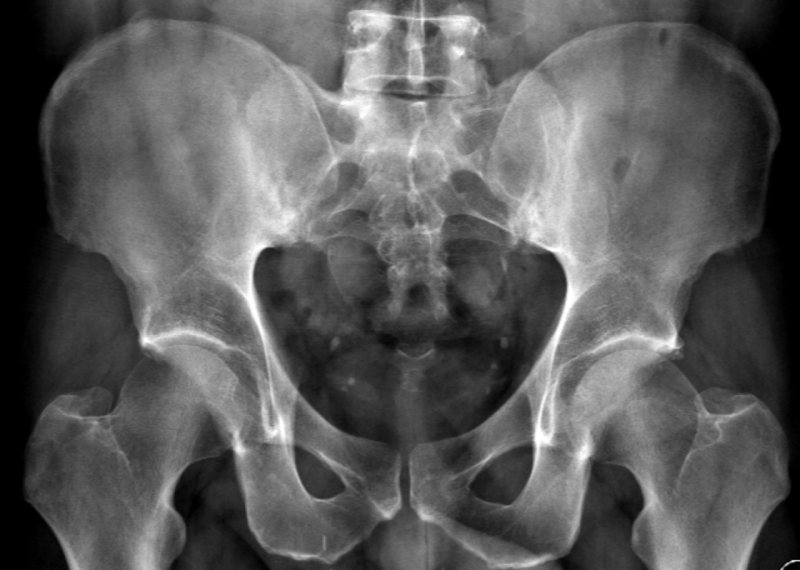

Chụp cộng hưởng từ (MRI) là một phương pháp tạo ra hình ảnh rất rõ nét về các cơ quan và cấu trúc bên trong cơ thể. MRI sử dụng nam châm lớn, sóng vô tuyến và máy tính để tạo ra hình ảnh chi tiết. Nó không sử dụng tia X (bức xạ) nên thường được lựa chọn khi cần chẩn đoán bệnh lý ở não bộ. (4)

Kết quả chụp cộng hưởng từ cho thấy mức độ tổn thương của khớp cùng chậu, cơ, dây chằng, vết nứt gãy nhỏ tại khớp. Với phương pháp này, bác sĩ có thể chẩn đoán mức độ viêm của khớp cùng chậu từ giai đoạn khởi phát mà chụp X Quang và CT không phát hiện được.